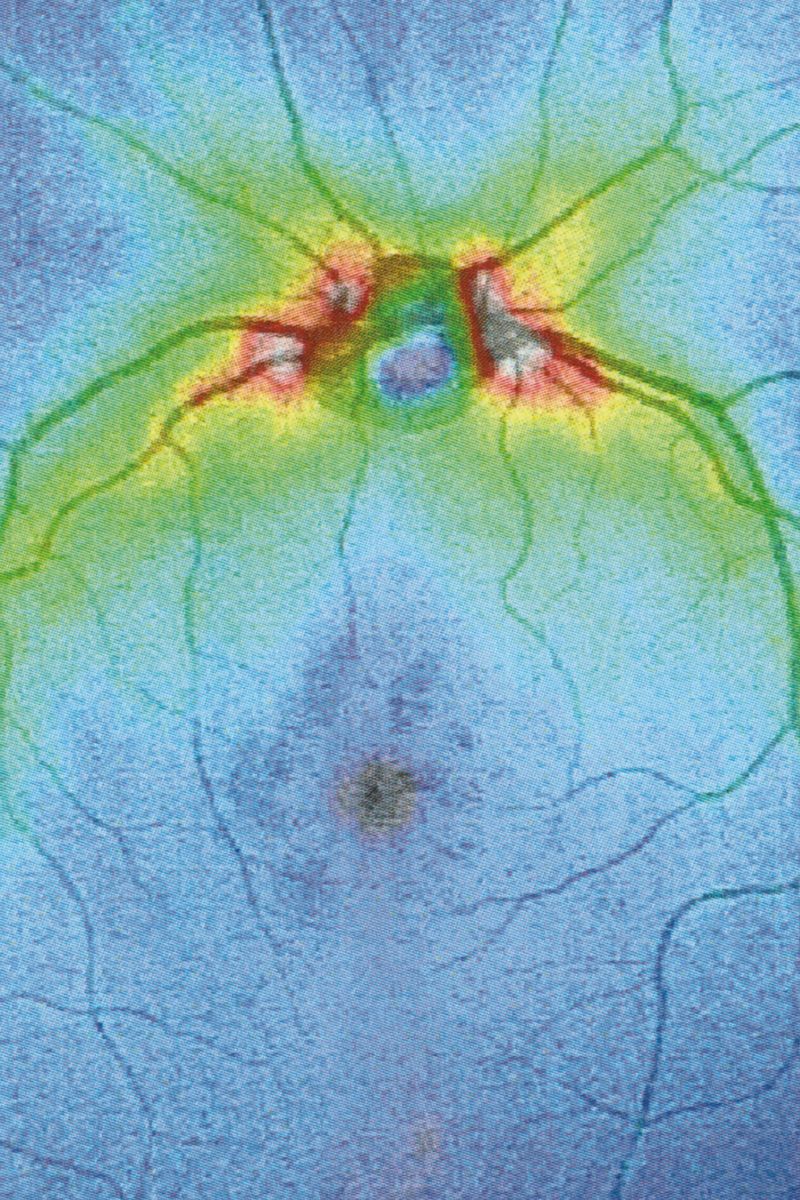

© Eugenio Pancaldi - La Fototeca, Bologna.

La Fototeca, Bologna.